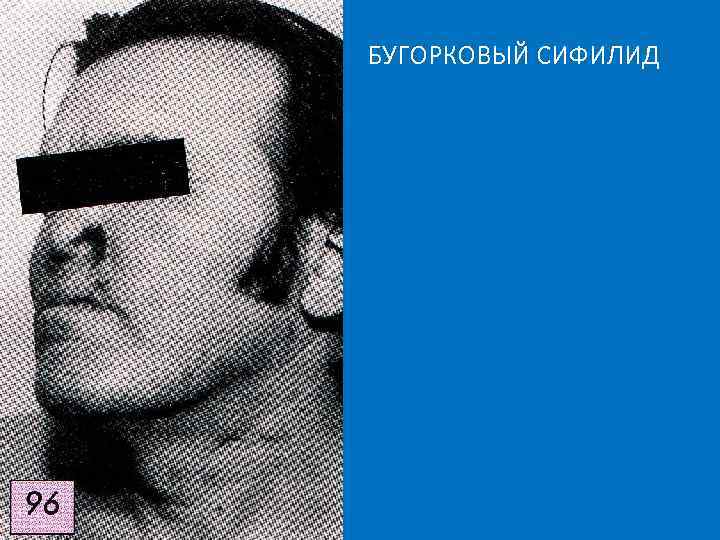

Поражения кожи представлены бугорковым и гуммозным сифилидами, и поздней третичной розеолой. БУГОРКОВЫЙ СИФИЛИД • залегает в сетчатом слое дермы, • полушаровидной формы, • размером с вишневую косточку, • тёмно‑ красного или синюшно-красного цвета, • поверхность гладкая, блестящая. q Спустя несколько нед - мес бугорок размягчается и изъязвляется с образованием округлой язвы с валикообразными краями. q Дно язвы очищается от распада, покрывается грануляциями и превращается в пигментированный по периферии атрофический рубец, на котором никогда не возникает новых высыпаний. q Группа рубцов имеет мозаичный вид.

Клинические разновидности бугоркового сифилида: • Сгруппированный – бугорки расположены кучно, но изолированно. • Серпигинирующий ( «ползучий» ) – на смежных участках вновь появляются новые бугорки. • Площадкой – они сливаются, отдельных бугорков не видно. • Карликовый – от просяного зерна до вишнёвой косточки.

БУГОРКОВЫЙ СИФИЛИД